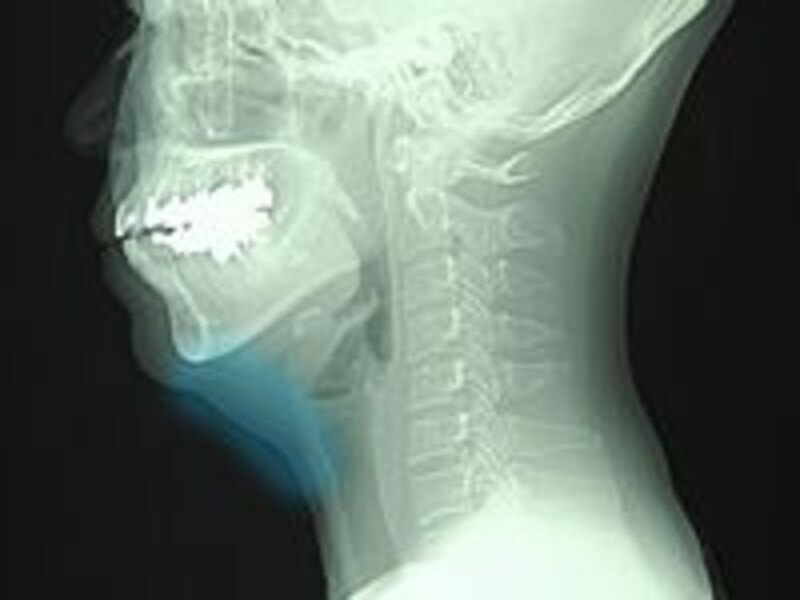

| クリニックで撮影したレントゲン写真。ガイドが水色に塗った部分に脂肪がたっぷりたまります |